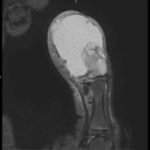

A 12-year-old male presented to the emergency department with right thumb pain and a mass for four months (see images). He denied fevers, chills, change in appetite, or fatigue. He noted that the lesion was growing and “bleeds easily if bumped.” He denied any trauma to the thumb, except “hitting it” months ago while in football practice.

Magnetic resonance imaging (MRI) showed an “expansile, destructive solid and cystic mass with aggressive…characteristics…” (see images). Tissue biopsy confirmed a giant cell tumor arising from the bone. The patient underwent a debulking procedure, and later a distal amputation. Follow-up on pathology showed negative margins.